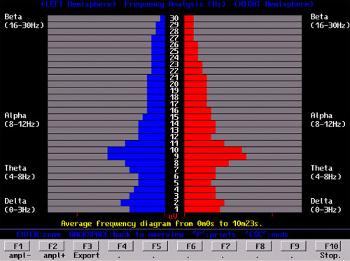

As imagens abaixo sintetizam 200 metros de dados lineares de eletroencefalograma (EEG).

Estas cores representam a média das frequências das ondas cerebrais representando toda a duração do teste. No caso abaixo, de 4, 12 e 4 minutos.

A escala vertical no centro mede a frequência cerebral de 1 Hertz a 30 Hertz em divisões de 1 Hertz.

A distância horizontal para fora do centro mede o poder da onda cerebral.